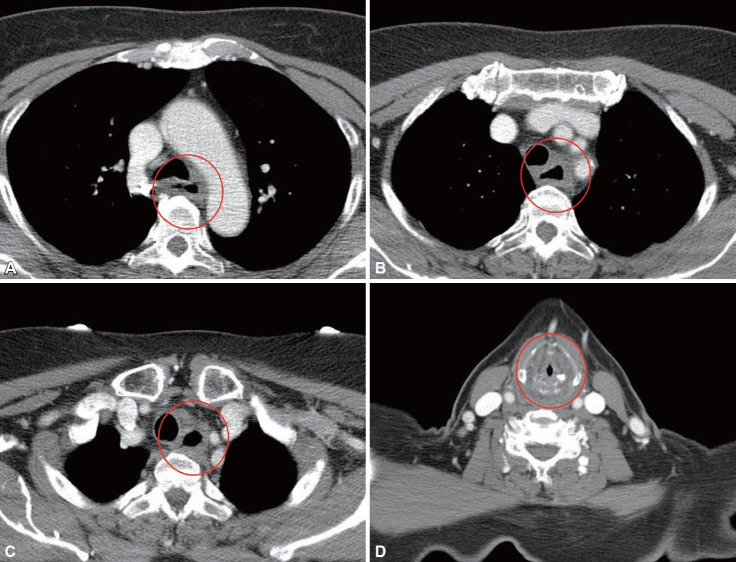

上消化道的腐蚀性损伤,特别是由碱性物质引起的损伤,往往比摄入酸性物质后所观察到的组织损伤更严重和更深。我们报告一个严重的腐蚀性损伤的情况下,摄入氯漂白剂(200毫升),一种碱性剂。初步内镜检查显示严重的食管和胃损伤伴坏死(Zargar分级3b),无任何穿孔迹象。治疗方案包括延长禁食加全肠外营养,住院1个月后通过空肠造口开始肠内喂养。患者住院和出院几次,直到我们观察到完全愈合的食管和胃。损伤后4个月随访内镜检查显示食管壁改善;然而,严重的狭窄阻止了口服。因此,患者于伤后7个月行手术干预,包括食管切除术、全胃切除术、食管结肠空肠吻合术。自首次手术以来,由于吻合口漏、感染和狭窄,患者接受了大约一年的重复伤口翻修手术、经皮引流、重建和布根成形术。患者在初次损伤后接受了大约2.5年的口腔和空肠造口管喂养。早期内窥镜检查有助于确认该病例腐蚀性损伤的严重程度和预测预后。正如预期的那样,摄入碱性物质后的严重腐蚀性损伤与临床预后不良有关。诊断和治疗此病时应谨慎。

Corrosive injuries to the upper gastrointestinal tract, particularly those caused by alkaline substances, often result in more severe and deeper tissue injuries than those observed after ingestion of acidic substances. We report a case of severe corrosive injury following ingestion of chlorine bleach (200 mL), an alkaline agent. Initial endoscopic evaluation revealed severe esophageal and gastric injuries with necrosis (Zargar grade 3b), without any signs of perforation. The treatment plan included prolonged fasting with total parenteral nutrition, and enteral feeding was initiated via jejunostomy 1 month after hospitalization. The patient was hospitalized and discharged on several occasions until we observed complete healing of the esophagus and stomach. Follow-up endoscopy performed 4 months after the injury showed improvement in the esophageal wall; however, severe stenosis prevented oral intake. Therefore, the patient underwent surgical intervention, including esophagectomy, total gastrectomy, and esophagocolojejunostomy, 7 months post-injury. Since the initial surgery, the patient underwent repeat wound revision procedures, percutaneous drainage, reconstruction, and bougienation owing to anastomotic leakage, infection, and stenosis for approximately a year. The patient received oral and jejunostomy tube feeding for approximately 2.5 years after the initial injury. Early endoscopy was useful to confirm the severity and predict the prognosis of corrosive injuries in this case. Severe corrosive injuries following ingestion of alkaline substances are associated with poor clinical prognosis, as anticipated. Caution is warranted for the diagnosis and treatment of this condition.